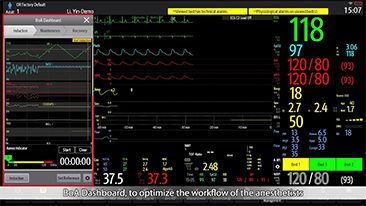

Resona 7, ĂŒstĂŒn dĂŒzeyde g?rĂŒntĂŒ kalitesine ek olarak, vaskĂŒler hemodinamik de?erlendirmesi i?in devrim niteli?indeki V Ak??? ile fetĂŒs CNS tan?lamas? i?in 3 boyutlu veri kĂŒmesinden dĂŒzlem g?rĂŒntĂŒsĂŒ alma konusunda en iyi birime sahip oldu?undan, klinik ara?t?rma yeterliklerini de art?rmaktad?r. En sezgisel, harekete dayal? ?oklu dokunmatik i?letim ile tĂŒm temel klinik ?zellikleri bir araya getiren Resona 7, ultrason yenili?i konusunda ger?ek anlamda yeni dalgalara ?ncĂŒlĂŒk ediyor.